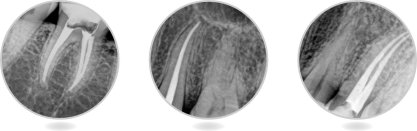

1.用充填筆封密根尖孔:

![]()

步驟1A用根管銼將根管備成所需的形狀,檢查根管長(zhǎng)度,選擇適合的主尖,充填在根管內(nèi)部。

步驟1B把充填筆頭放置在根管內(nèi)部4—7MM處,然后在合適的位置放上帶顏色的標(biāo)識(shí)膠墊。

步驟2將蘸有根管封密劑的主尖填入根管內(nèi)。

步驟3A把充填頭放入根管孔內(nèi),按住開(kāi)關(guān)按鈕加熱,切斷GP中間部位,然后將充填頭壓至距根尖孔6-9mm處,壓1.5-2秒鐘。

步驟3B松開(kāi)按鈕,使充填頭冷卻,同時(shí)繼續(xù)推動(dòng)充填頭并保持8秒鐘對(duì)根尖的擠壓,使根尖得到完全的充填。然后按住操作鈕1-1.5秒,再次開(kāi)啟DIA-PEN,將牙膠尖充填到距根尖孔4-7mm處。

步驟4使用充填器將剩余的充填料壓緊。